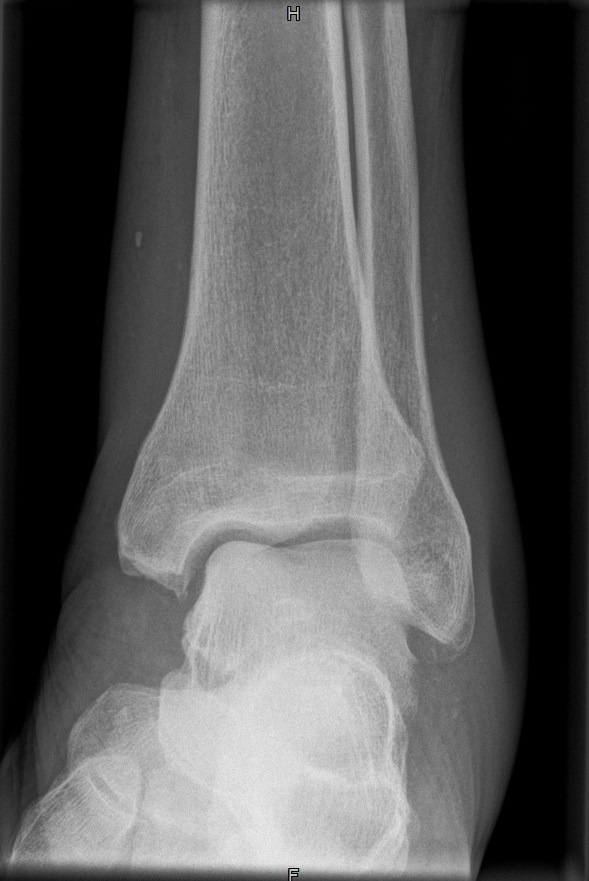

OSG seitlich

Fehler

Doppelkonturierung im vorderen Teil der Talusrolle. Die Fibula ist gegen dem Malleolus internus nach ventral verschoben. Die Längsachse des Talus ist verkürzt. Das untere Sprunggelenk kann nicht beurteilt werden.

Abhilfe

Keilkissen unter den Calcaneus legen bzw. Fuß flacher auf den Zehen auflegen lassen.